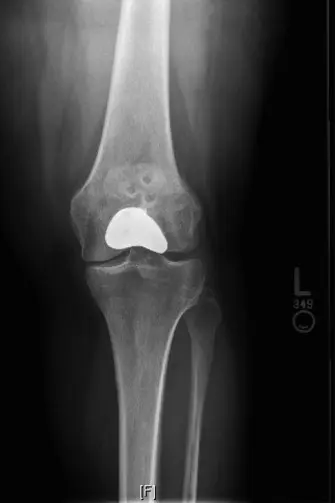

استبدال مفصل الرضفة الفخذي (PFA) هو تدخل جراحي متقدم لعلاج خشونة مفصل الرضفة الفخذي المعزولة والشديدة. يهدف إلى تخفيف آلام الركبة الأمامية عن طريق استبدال السطوح المتضررة فقط، مع الحفاظ على الأجزاء السليمة من الركبة، ويتم العلاج بإشراف خبراء مثل الأستاذ الدكتور محمد هطيف.

مع التقدم الكبير في جراحة العظام، ظهر "استبدال مفصل الرضفة الفخذي" (Patellofemoral Arthroplasty - PFA) كحل جراحي مستهدف ومبتكر. يقدم هذا الإجراء بديلاً يحافظ على المفصل، ويهدف إلى تخفيف آلام الركبة الأمامية عن طريق استبدال الأسطح المصابة فقط في مفصل الرضفة الفخذي، مع الحفاظ على حركة مفصل الظنبوب الفخذي السليم ووظيفة الحس العميق للركبة. هذا يعني أن الأجزاء السليمة من الركبة لا يتم المساس بها، مما يوفر نتائج وظيفية أفضل وشعورًا أقرب إلى الركبة الطبيعية.

- وضع ميرشانت أو شروق الشمس (Merchant/Sunrise View) (30-45 درجة ثني): تُعد هذه الأشعة حاسمة لتقييم المسافة المفصلية، وتضيق المساحة، والتكلسات العظمية (osteophytes)، والتغيرات التآكلية في مفصل الرضفة الفخذي.

- الهدف من الأشعة السينية: تأكيد وجود خشونة مفصلية (تضيق المسافة المفصلية، تصلب تحت الغضروفي، تكلسات عظمية) محصورة بشكل أساسي في مفصل الرضفة الفخذي، مع الحد الأدنى من التغيرات التنكسية أو عدم وجودها في مفصل الظنبوب الفخذي.